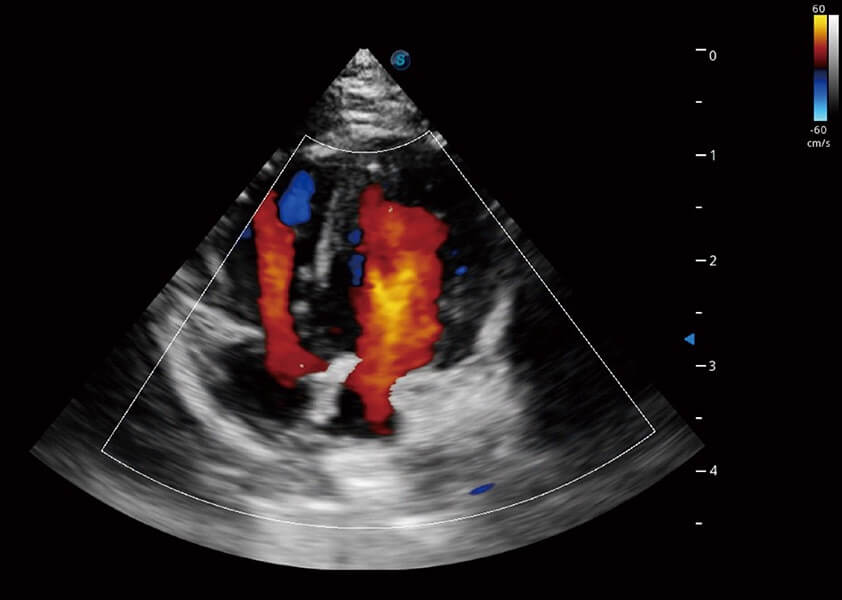

ProPet 60 作为一款高端台式动物超声设备,为动物医生的日常诊断提供了一系列贴合动物临床需求、解决临床实际问题的高级成像功能。凭借全系列高清探头,满足医生对腹部、心脏、生殖、浅表、肌骨等成像的所有需求,切实帮助您提升检查效率,提高诊断信心。

动物是人类最亲密的朋友和最值得信赖的伙伴。球速体育入口也一直致力于探索动物专用的超声影像解决方案。 全新推出的ProPet系列,是球速体育入口在动物超声影像智能化、专业化、精准化的一次跨越式革新。动物不能用言语来表述自己的不适,通过超声影像,ProPet系列搭建了动物医生与不同物种沟通的“桥梁”,为动物医生注入了“治愈之力”。